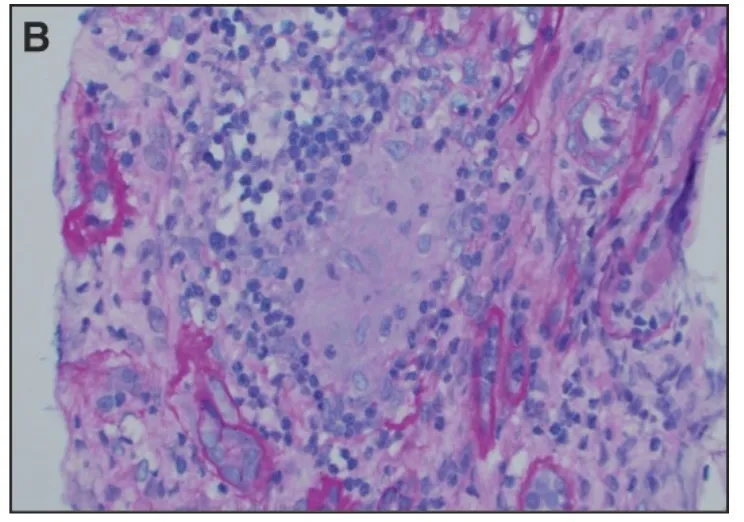

Uma causa incomum de hematúria glomerular intermitente!

Hematúria pós infecção, caso clínicos para auxiliar no entendimento de causas glomerulares comuns e raras...